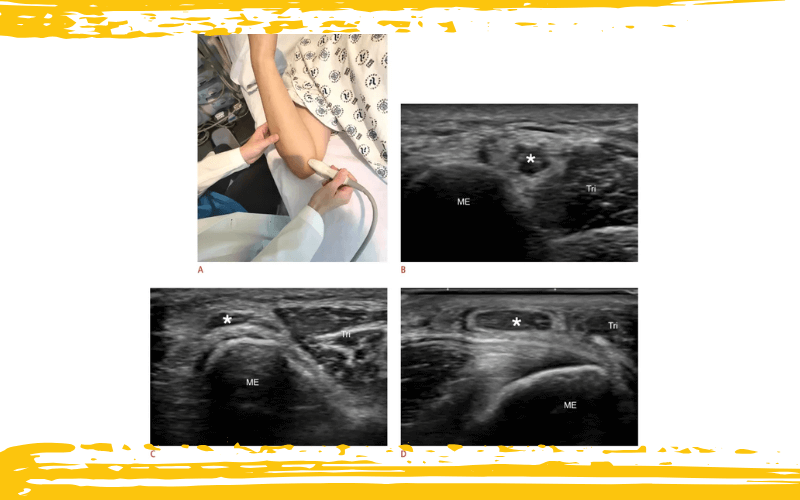

Posicionamiento del paciente y colocación del transductor para la evaluación de la inestabilidad del nervio cubital, junto con las imágenes ecográficas correspondientes.

A. Al colocar el transductor sobre el túnel cubital con presión mínima, el explorador puede observar si el nervio cubital se desplaza fuera del túnel cubital durante la flexión del codo.

B–D. Imágenes ecográficas en eje corto obtenidas a nivel del codo que demuestran las diferentes posiciones del nervio cubital durante la flexión del codo.

B. En un varón de 28 años, el nervio cubital (asterisco) se localiza posterior al epicóndilo medial (ME), que corresponde a su posición habitual durante la flexión del codo.

C. En una mujer de 29 años, el nervio cubital (asterisco) se encuentra subluxado sobre el vértice del epicóndilo medial (ME) durante la flexión del codo.

D. En un varón de 58 años, el nervio cubital (asterisco) aparece completamente luxado, situándose anterior al epicóndilo medial (ME) durante la flexión del codo.

Tri: tríceps braquial.